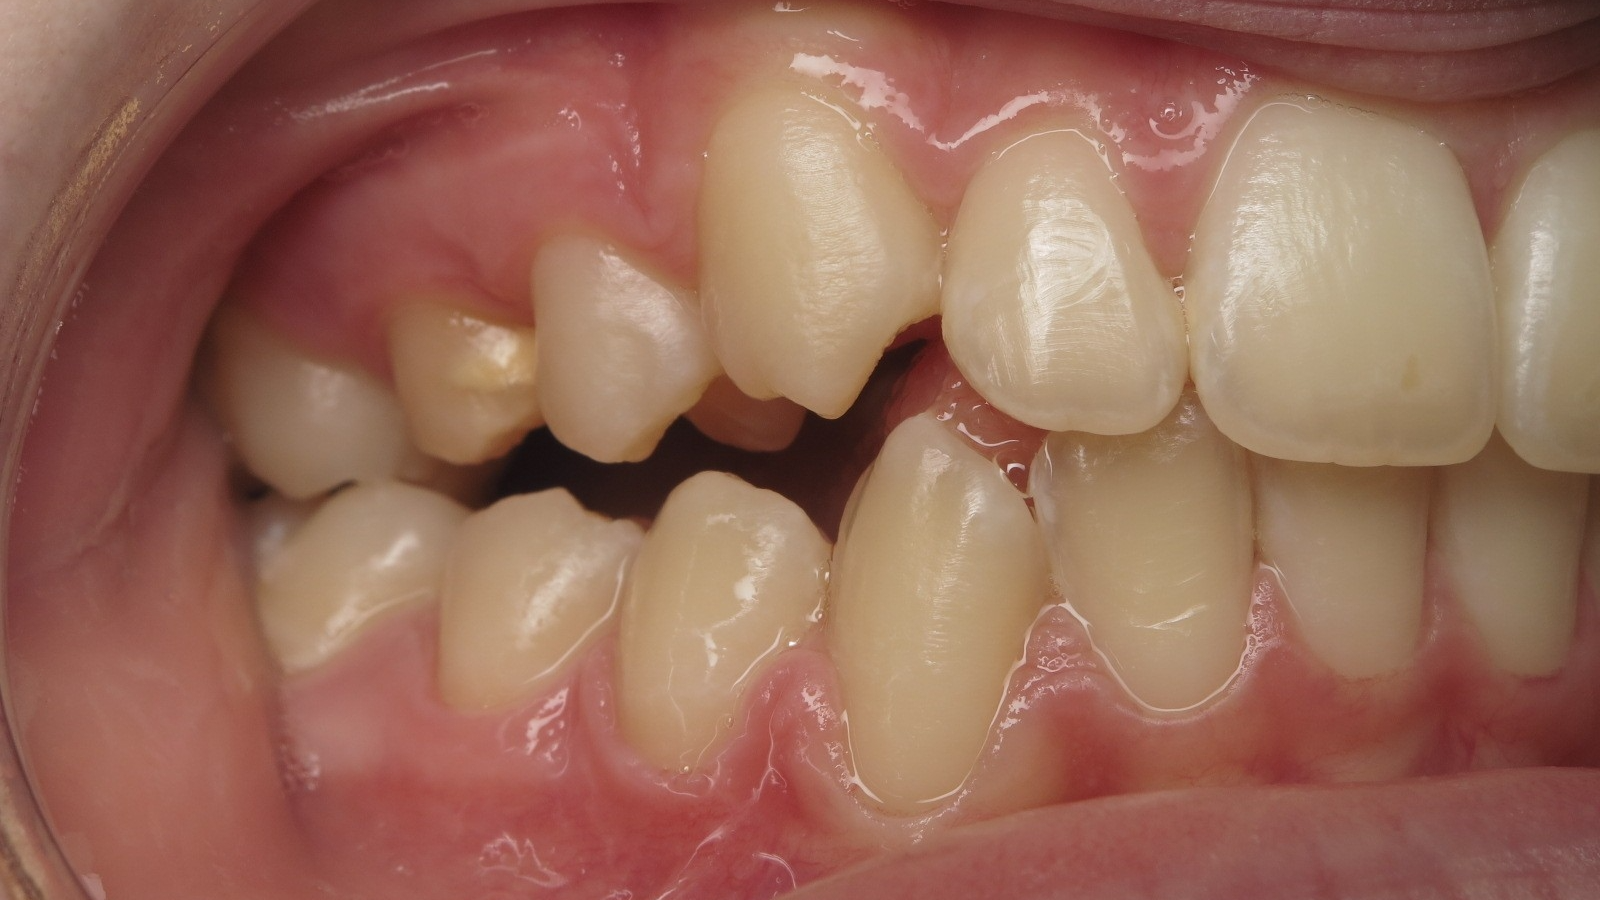

appareillage mobile

sectionnel multibagues

bilan début fin de traitement